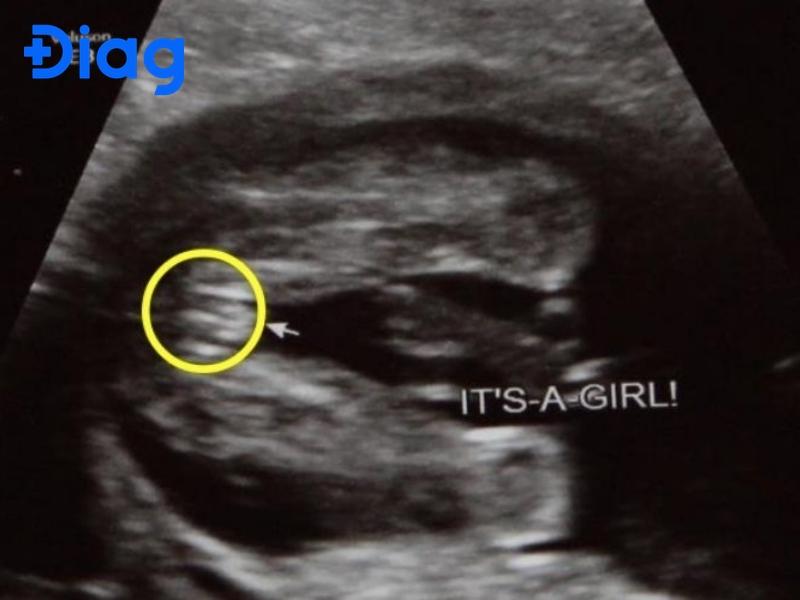

Hình ảnh siêu âm bé gái như thế nào? Hình ảnh siêu âm con gái chủ yếu dựa trên việc quan sát cấu trúc bên ngoài của bộ phận sinh dục khi thai đủ lớn. Trên màn hình siêu âm, bác sĩ thường tìm dấu hiệu đặc trưng của bé gái, thường được mô tả […]